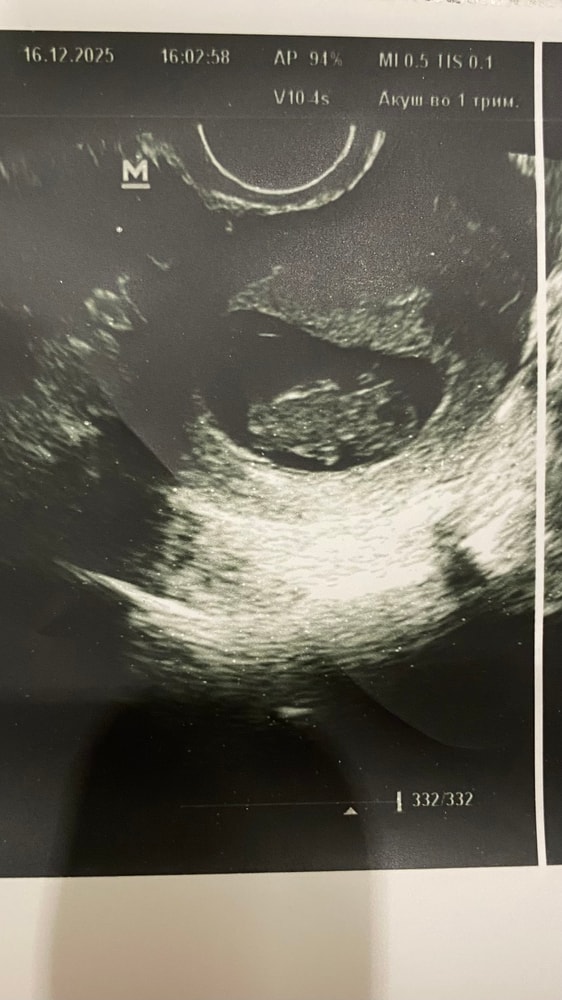

Сегодня сдавала анализы в ЖК для постановки на учет, там же сделали узи.

ПЯ 35,7 мм (соответствует 7 нед 4 дн)

ЖМ 4,2 мм

КТР 23,3 мм (соответствует 9 нед)

Сердцебиение 156 уд/мин.

Миометрий в гипертонусе.